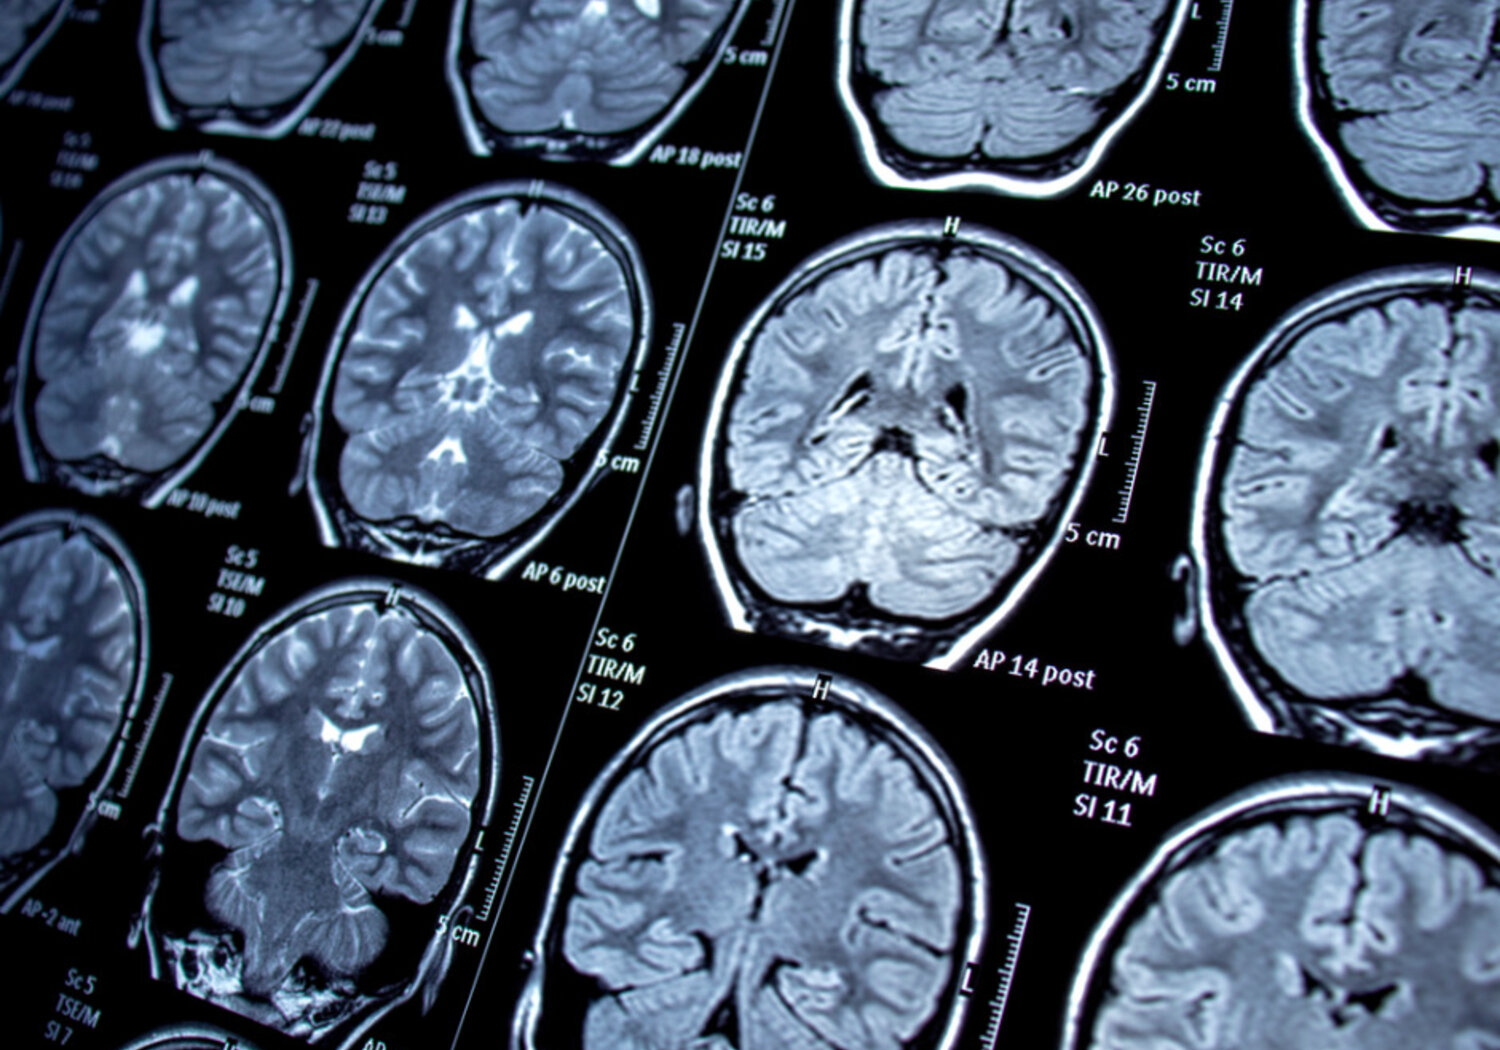

MRI scans of the brain

Magnetic resonance imaging (MRI) uses radio waves and large magnetic fields to help identify conditions ranging from damaged ligaments to cancer. Around 40 million MRI scans are performed each year in the EU, but the size and cost of scanners means that not all European citizens have equal access to this form of medical diagnosis.

‘Low-field MRI’ is a portable form of the standard MRI scanner, opening opportunities to provide treatment at a patient’s locality. However, these machines currently lack metrological traceability on the results they give. These instruments also lack the accredited documentation blueprints of hardware and software required by the EU’s Medical Device Regulation (EU)2017/745 (MDR).